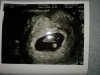

Gratulacje i zdrówka dla wasMelduję się po wizycie [emoji6]

Serduszko pięknie bije [emoji3590]

Super gratulujęOk, już po wizycie, wszystko książkowo, termin z miesiączki podtrzymanyZobacz załącznik 1206751